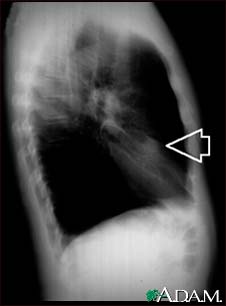

Lung nodule, right middle lobe - chest X-ray

This is a chest x-ray (CXR) of a nodule in the right lung.